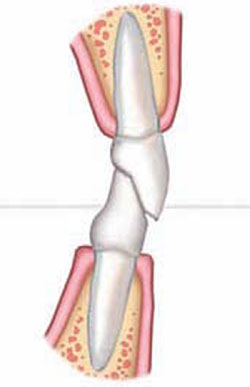

Severe Dental Erosion

The 36-year-old female in Figure 2A wanted a “prettier smile.” Figure 2C and Figure 2D show a combination of the problems of tooth destruction from incisal wear and lingual erosion from bulimia.10 Severe erosion cases present a unique problem for the orthodontist. Not only must he or she establish the correct mesio-distal tooth positions within the arch, but the orthodontist must also develop the correct interarch relationships and maintain them with much of the lingual and incisal tooth structure of the upper incisors missing (Figure 1C). Establishing spaces in orthodontics to compensate for malformed or worn teeth is sometimes relatively easy; maintenance is extremely difficult.1 Elastics would move the anteriors together easily (as would natural eruptive forces if left unchecked); therefore, these normally positive forces become negative for the orthodontist until the tooth structure is replaced. Thus, the intermediate restoration of the upper anterior teeth after initial orthodontic spacing removes the orthodontist’s guesswork that would otherwise be involved in determining the ideal positions of the teeth 3-dimensionally. The orthodontist in this case exaggerated the spacing of the teeth to give the restorative dentist better access to create ideal tooth morphology and to make placement and finishing of the composite-resin build-ups easier (Figure 1C, Figure 2F, and Figure 2G) At this point, the restorative goal was not to develop ideal occlusal or proximal relationships yet.

As in the previous case, warmed composite resin was bonded directly onto the incisal and lingual surfaces of teeth Nos. 6 to 11. The use of a wax-up and clear VPS matrix provided greater control and facilitated the chairside procedure (Figure 2E through Figure 2G ). With this technique, chair-time and costs were reduced and the VPS matrix eliminated the traditional step of model duplication of the wax-up and plastic matrix formation, saving laboratory time as well. This approach also preserves vital tooth structure at the final restorative phase by protecting against overreduction of the tooth for porcelain placement where tooth structure was already missing. Orthodontic treatment was continued, removing the arch wire only temporarily for composite-resin placement. The orthodontist or restorative dentist has the opportunity to reshape the composite-resin buildups as needed to create ideal form as the proximal contacts develop and the interincisal relationship finalizes. Occlusal and frontal views of the composite-resin build-ups are shown in Figure 2F through Figure 2G. The orthodontist can more predictably create an ideal relationship of the anterior teeth and the patient appreciates the cosmetic improvement in the newly developed smile (Figure 2H through Figure 2I).

Figure 2A Smile view showing incisal wear and open buccal corridors. |  Figure 2B Retracted view of worn incisal edges with uneven gingival margins. Patient exhibits classic signs of bulimia: lingual erosion of upper incisors and premolars. | ||||||

Figure 2C Initial orthodontics to create space for intermediate restorations.Note the exaggerated spacing of the anterior upper teeth.Alignment of the gingiva and initial leveling. |  Figure 2D Occlusal view depicts severe destruction of lingual tooth structure. The orthodontist has provided access to perform restorative procedures more easily. | ||||||

Figure 2E Clear VPS matrix from waxup formed on model.Matrix loaded with warm composite resin and pressed into place. Light curing of composite resin directly through matrix. |  Figure 2F Completed lingual view of ideal anatomic form of teeth Nos. 6 to 11. | ||||||

Figure 2G Frontal smile showing incisal edges immediately after placement. |  Figure 2H Smile view 3 months after bracket repositioning shows improved esthetics and even gingival architecture.Note the filling out of the buccal corridors. | ||||||

Figure 2I Retracted view after orthodontic refinement. | |||||||